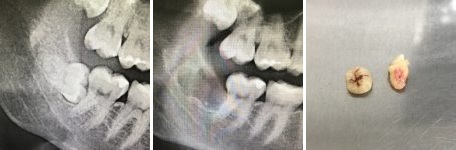

А для того, что ортопантомография (ОПТГ, обзорный или панорамный снимок зубов), является плоскостным, а значит происходит наложение каждой детали снимка послойно друг на друга. Следовательно, рассмотреть объект исследования, в частности, область зуба мудрости, расположенного рядом нижнечелюстного нерва, во всех плоскостях, под иным углом или другой проекции невозможно. КЛКТ (Конусно-лучевая компьютерная томография), напротив дает нам такую возможность.